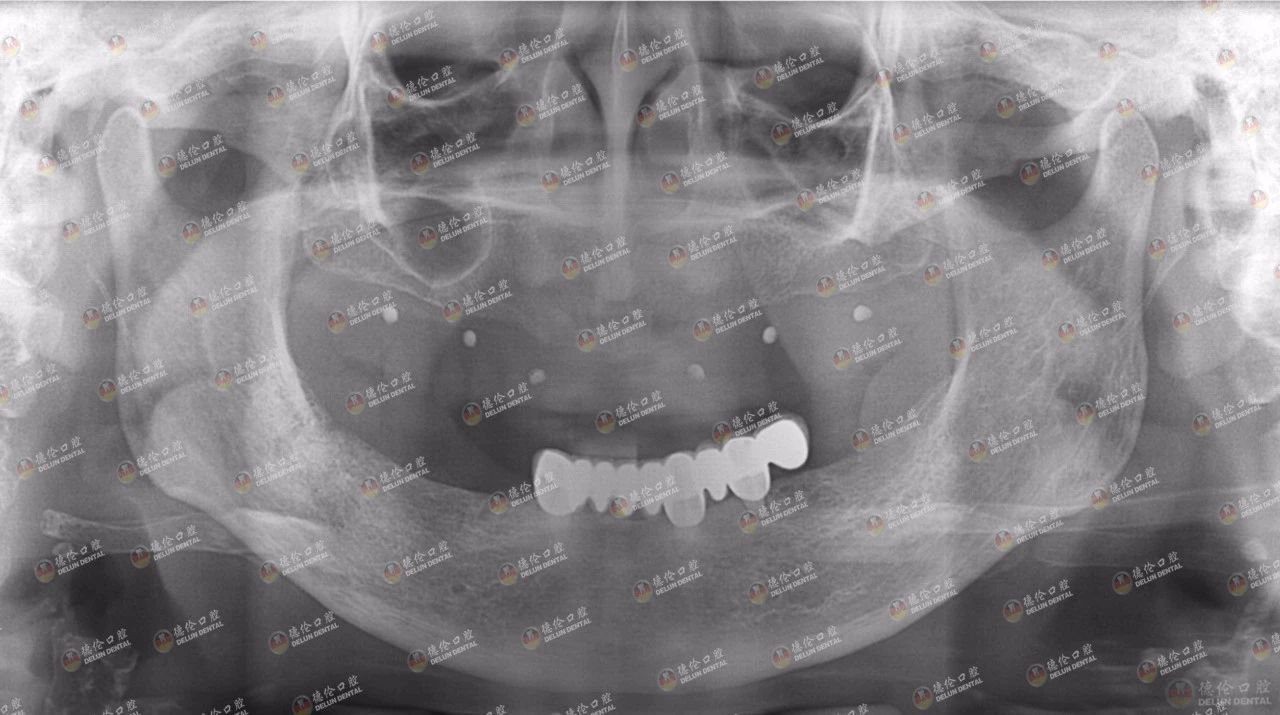

吴女士来德伦口腔诊疗时的牙片显示,只剩左下颌的种植牙,骨量不足

“吴女士来院时上颌和下颌右侧的烤瓷桥已经戴不住了,而且牙槽骨也已经吸收了一部分,因为在外院不太愉快种植经历,让吴女士对种植牙有些恐惧。”程武主任对吴女士第一次来院时的印象尤为深刻——无法直面无牙可用却又恐惧种牙手术。